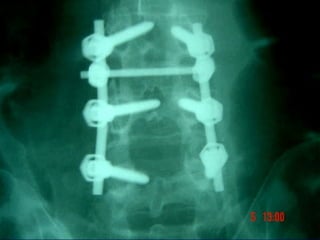

RECENTES AVANÇOS

A CIRURGIA DE COLUNA ESTÁ

SE TORNANDO UMA DISCIPLINA

SEPARADA INCORPORANDO

TÉCNICAS ORTOPÉDICAS E

NEUROCIRURGICAS